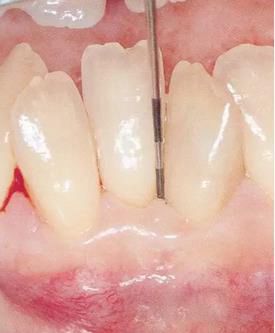

▲圖2

牙位異常例②。牙體傾斜。